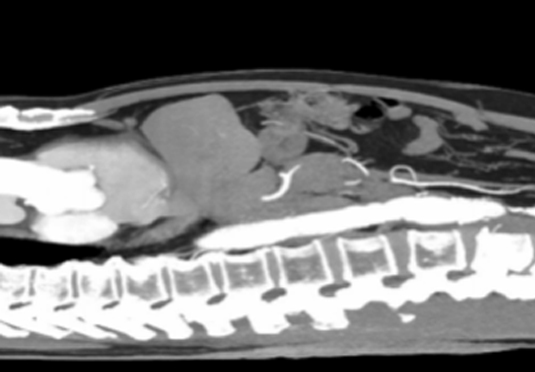

微創(chuàng)射頻消融術

適用于微創(chuàng)射頻熱消融術治療患者,引進權威醫(yī)療團體輔助引流。